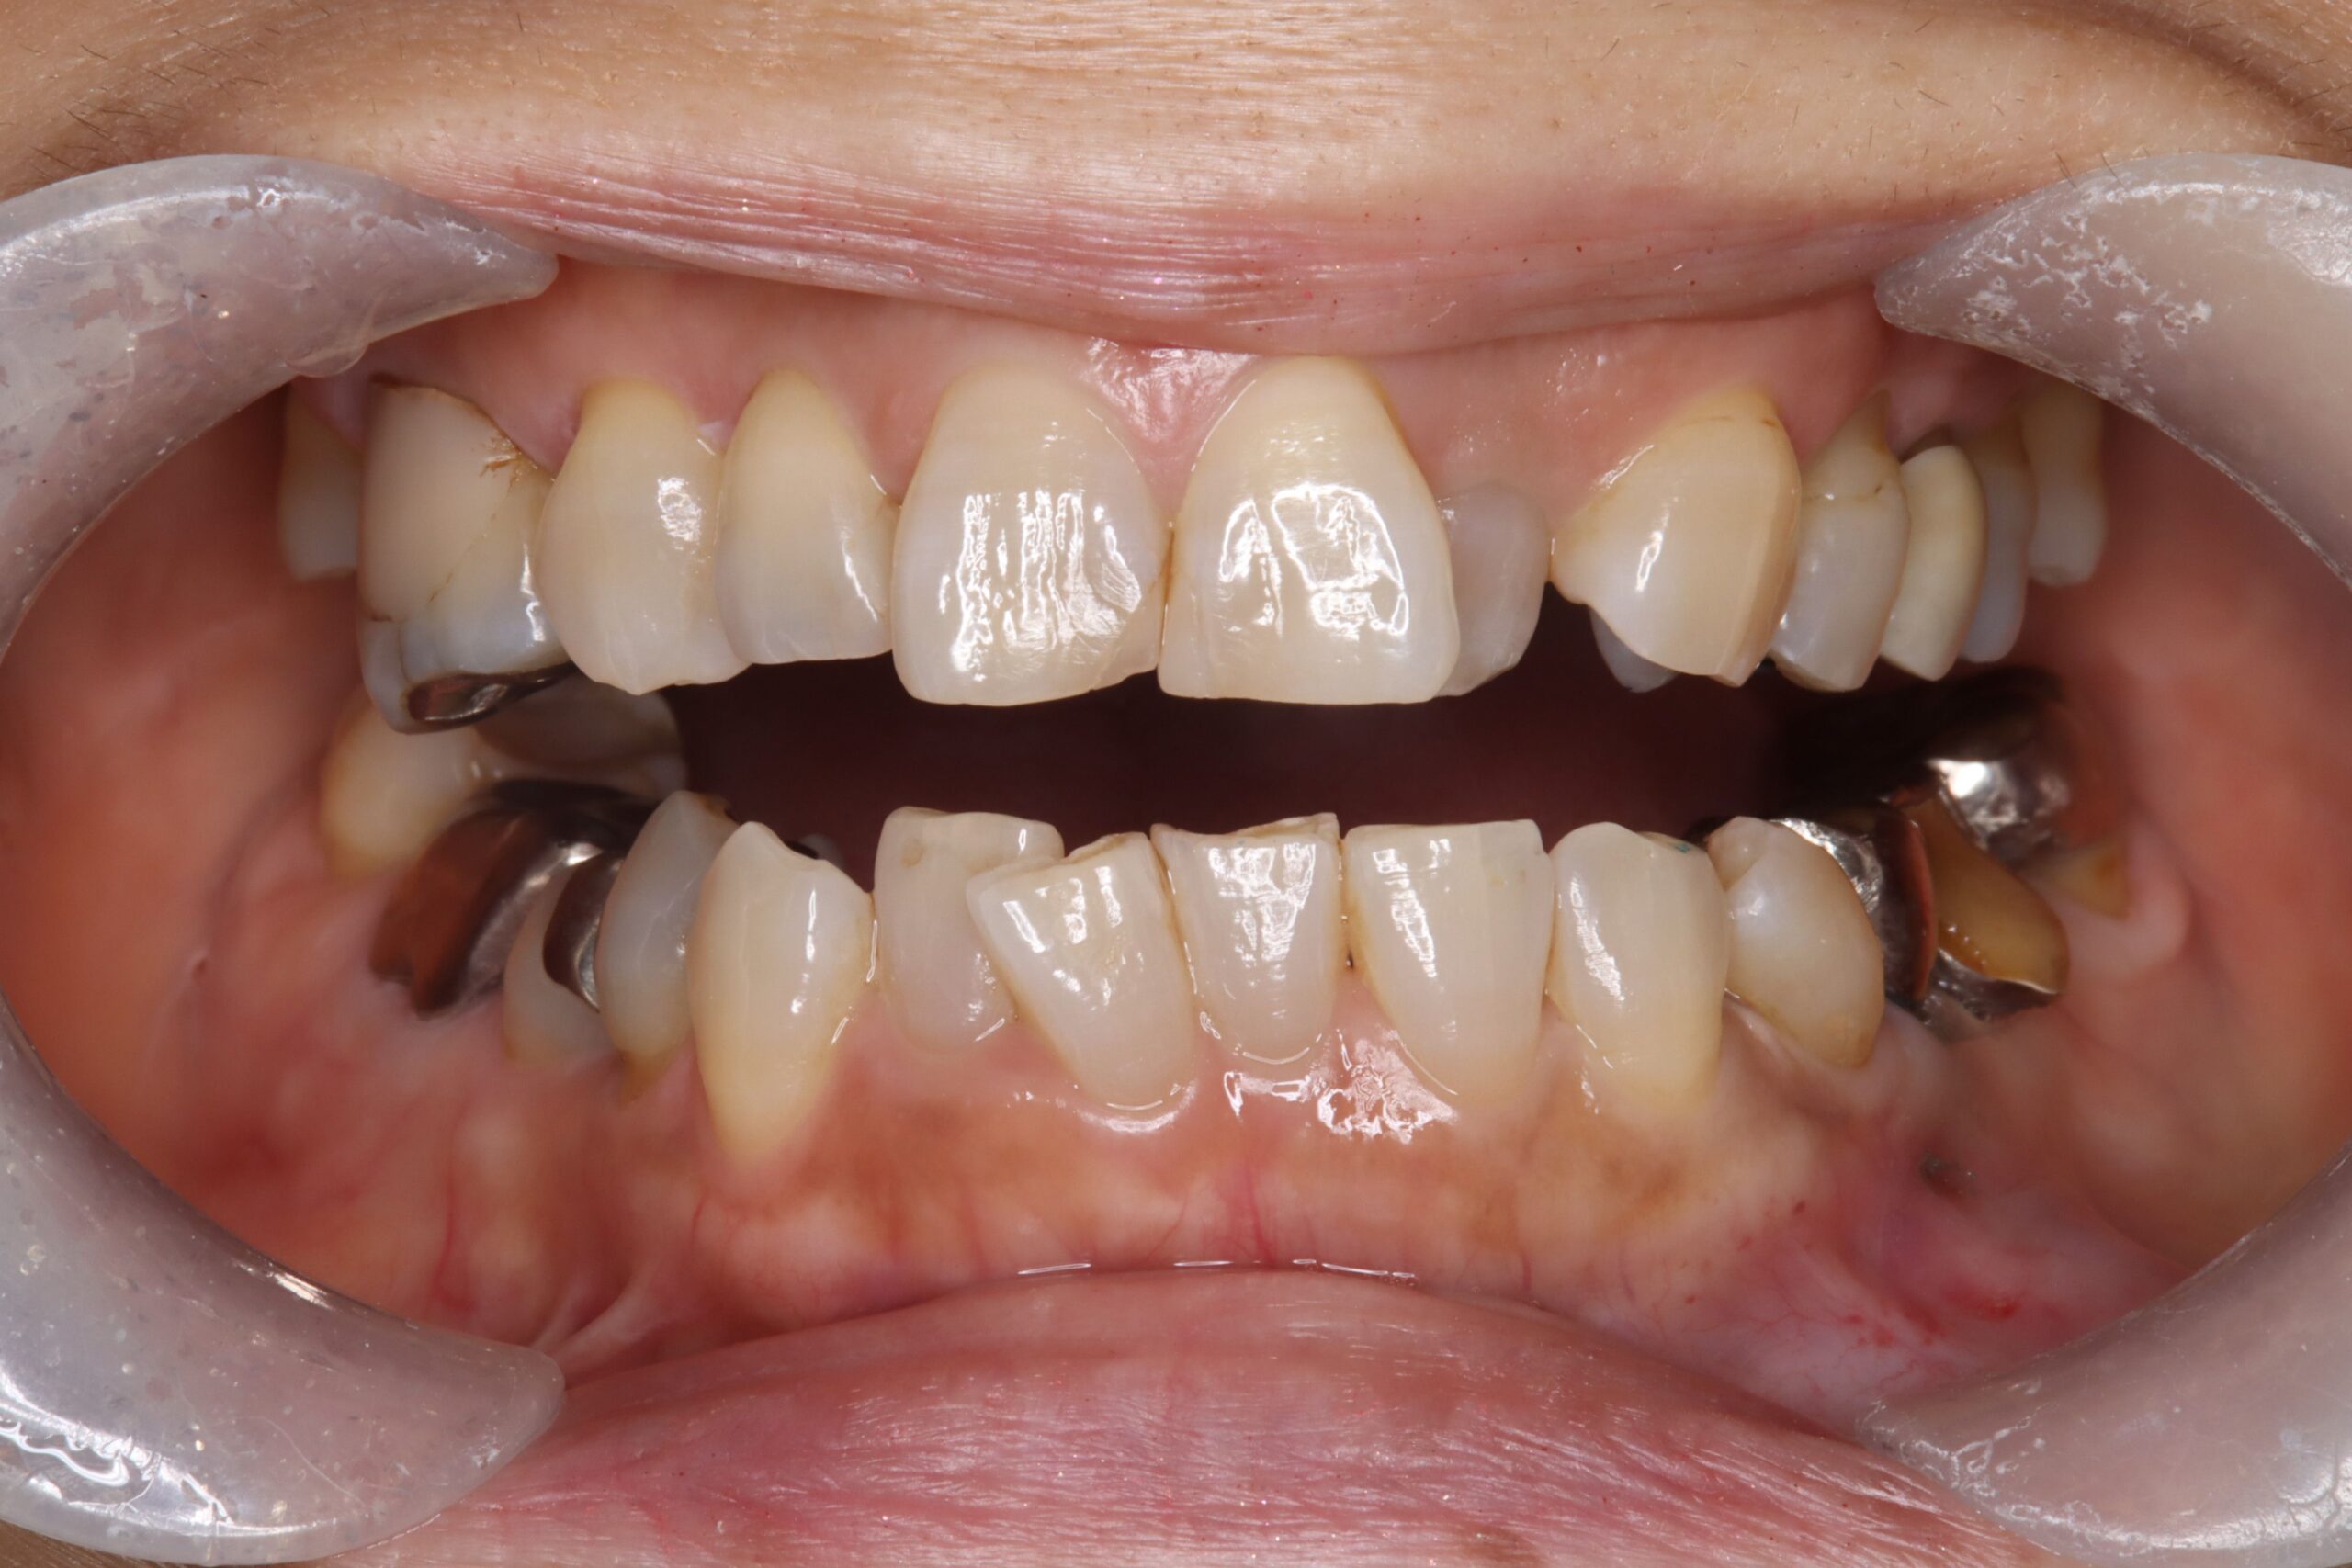

Orthodontics

自信が持てる

歯並びへ

歯並びが気になる方は是非ご相談ください。当院では、矯正歯科治療を専門とする歯科医師の診断のもと、ワイヤー矯正だけでなく、目立ちにくい透明のマウスピース矯正も提供いたします。歯並びが改善すると審美的なメリットだけでなく口腔機能へも好影響があります。ずっと健康にご自分の歯を保つためにも気になった今、矯正歯科治療を始めませんか?